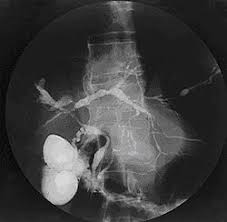

- It is a rare, long-term disease of the liver caused by inflammation of tubes in the liver called bile ducts.

- These ducts carry bile (a fluid that helps to digest fats) from the liver, where bile is produced, to the gallbladder, where it is stored, and to the small intestine, where it aids in digestion.

- Scarring and narrowing of bile ducts leads to liver damage.